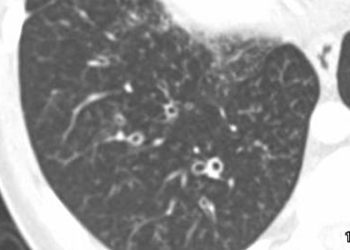

Image: PD 1. Neutrophil elastase activity in bronchoalveolar lavage fluid at 3 months is a risk factor for persistent bronchiectasis ...